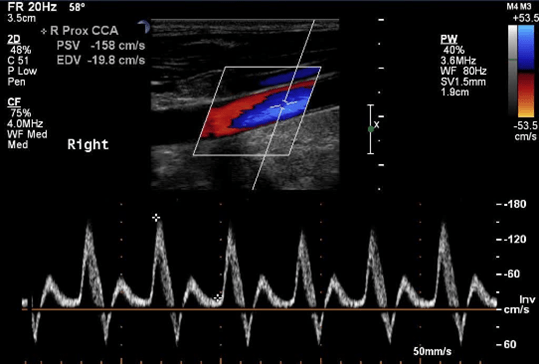

What is present in this image?

Can it be corrected via the machine?

flow reversal, no because it is not caused by machine settings.